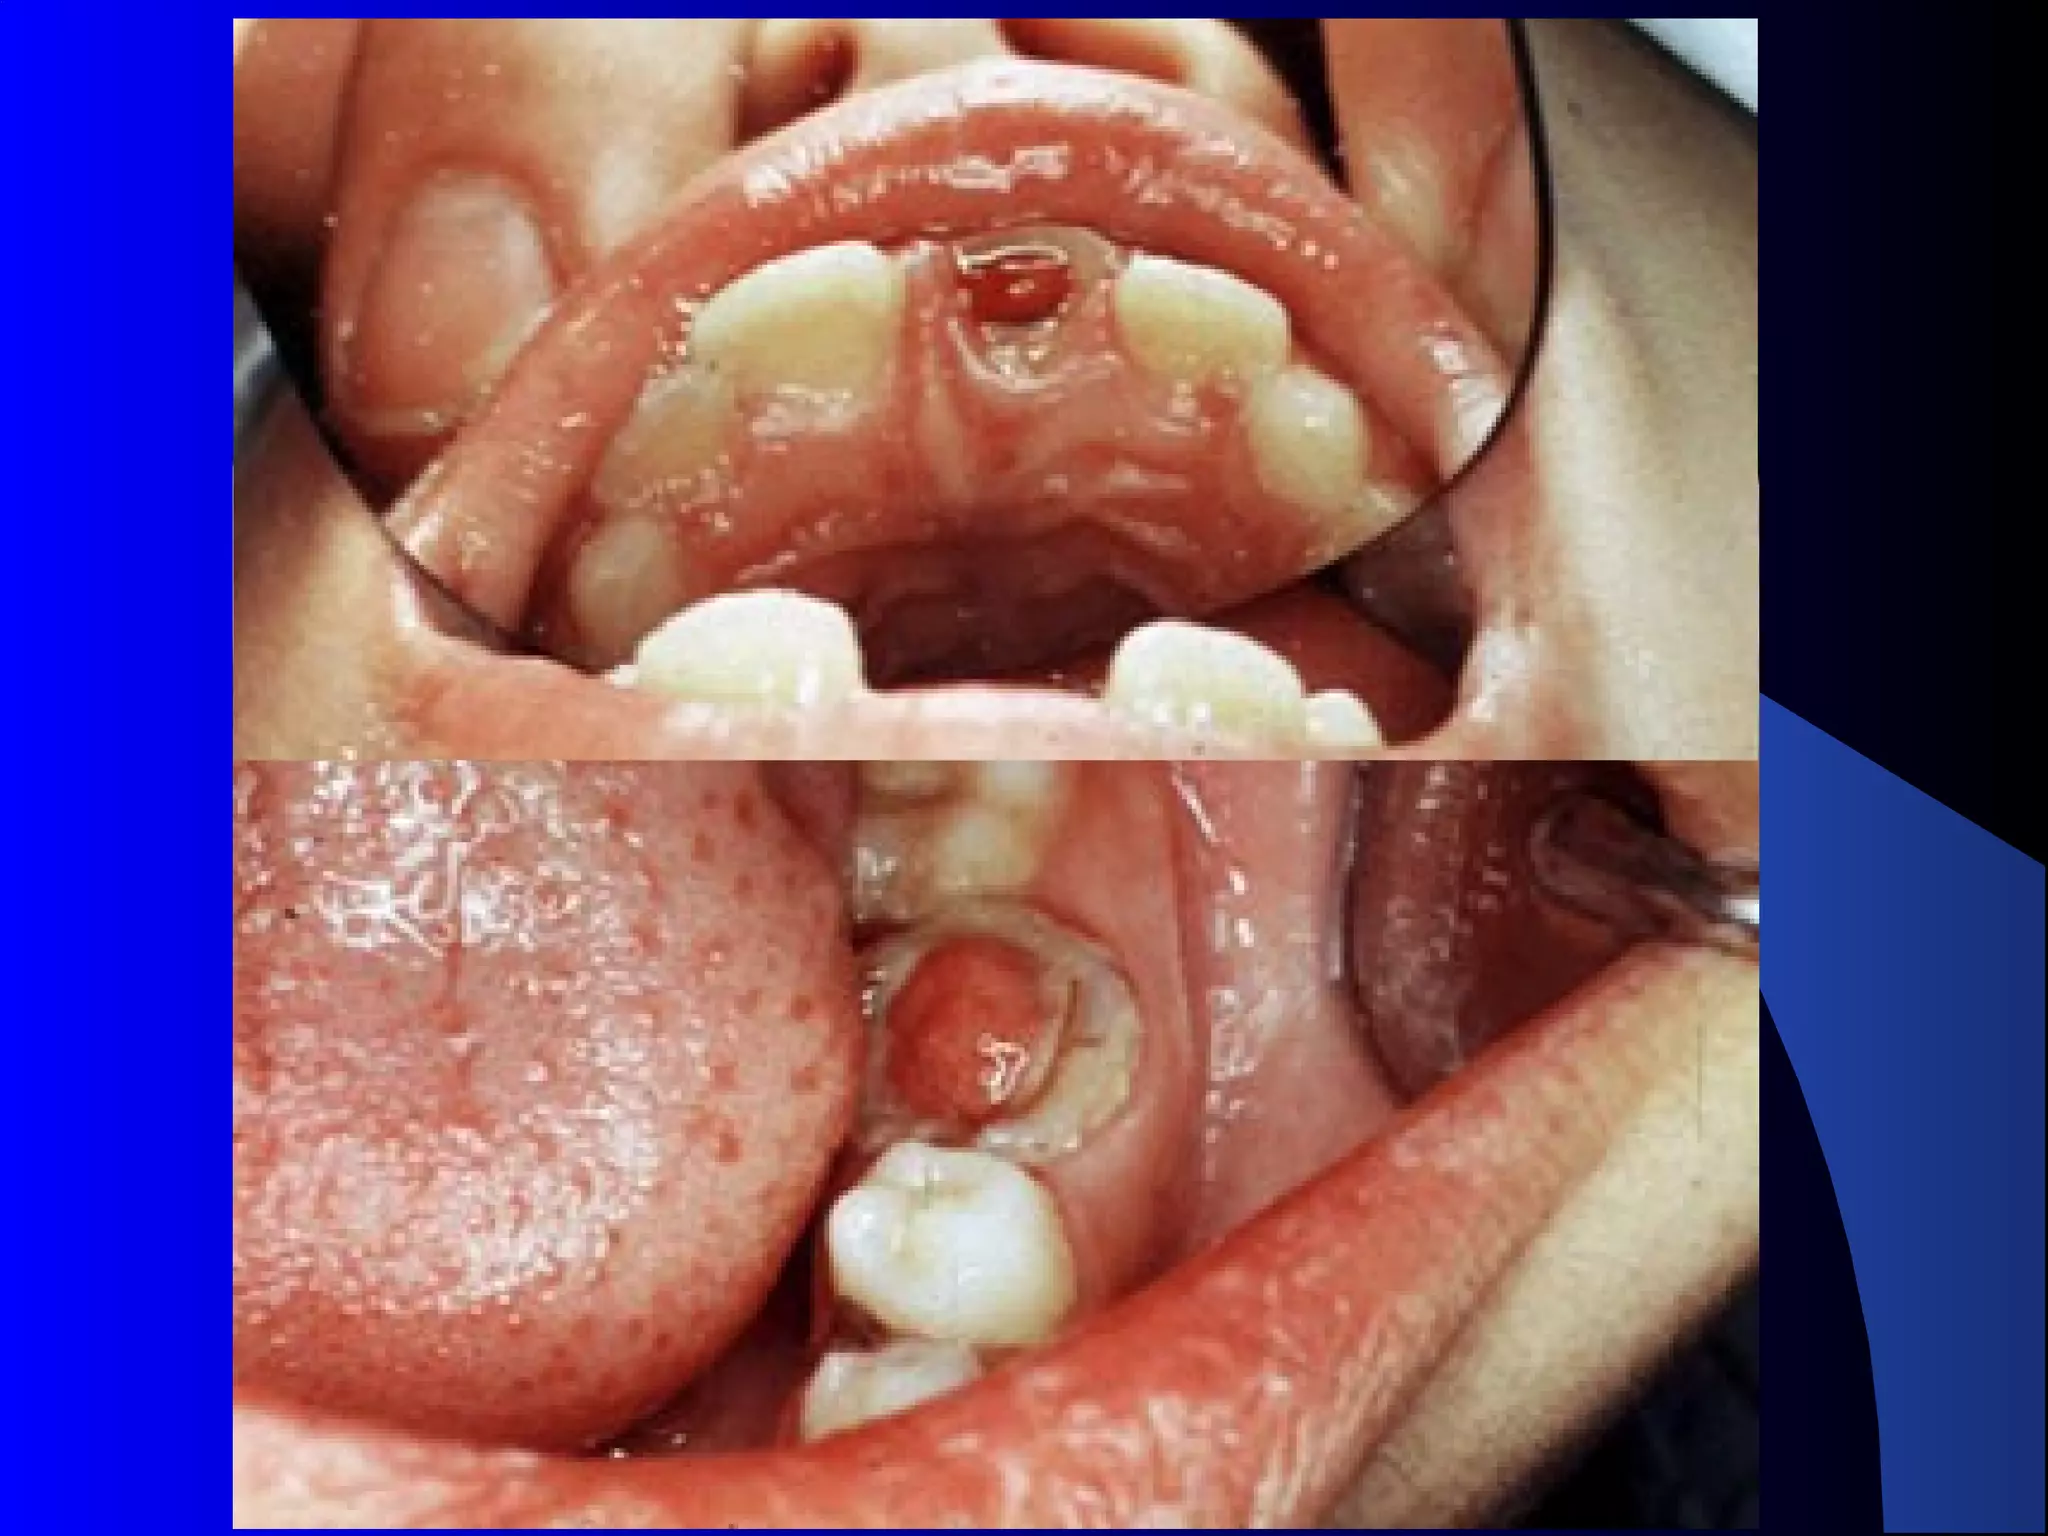

Chronic Hyperplastic Pulpitis

Pulp Polyp

Etiology:

Opened cavity.

 Starts as chronic or acute.

 Wide apical foramen [Children].

Clinical

Features:

Red pinkish soft nodule protruding into the

cavity.

 Almost in children and young adults.

 Relatively insensitive to manipulation.

 Most common in deciduous molars.

 Must be differentiate from gingival polyp.